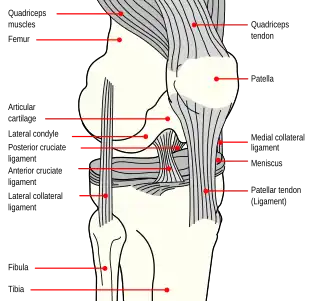

Structure

The knee is a modified hinge joint, a type of synovial joint, which is composed of three functional compartments: the patellofemoral articulation, consisting of the patella, or "kneecap", and the patellar groove on the front of the femur through which it slides; and the medial and lateral tibiofemoral articulations linking the femur, or thigh bone, with the tibia, the main bone of the lower leg.[6] The joint is bathed in synovial fluid which is contained inside the synovial membrane called the joint capsule. The posterolateral corner of the knee is an area that has recently been the subject of renewed scrutiny and research.[7]

Ligaments

The ligaments surrounding the knee joint offer stability by limiting movements and, together with the menisci and several bursae, protect the articular capsule.[19]

Intracapsular

The knee is stabilized by a pair of cruciate ligaments. These ligaments are both extrasynovial, intracapsular ligaments.[20] The anterior cruciate ligament (ACL) stretches from the lateral condyle of femur to the anterior intercondylar area.[13] The ACL prevents the tibia from being pushed too far anterior relative to the femur.[13] It is often torn during twisting or bending of the knee.[21] The posterior cruciate ligament (PCL) stretches from medial condyle of femur to the posterior intercondylar area. This ligament prevents posterior displacement of the tibia relative to the femur.[13] Injury to this ligament is uncommon but can occur as a direct result of forced trauma to the ligament.

Extracapsular

The patellar ligament connects the patella to the tuberosity of the tibia. It is also occasionally called the patellar tendon because there is no definite separation between the quadriceps tendon (which surrounds the patella) and the area connecting the patella to the tibia.[23] This very strong ligament helps give the patella its mechanical leverage[24] and also functions as a cap for the condyles of the femur. Laterally and medially to the patellar ligament, the lateral and medial retinacula connect fibers from the vasti lateralis and medialis muscles to the tibia. Some fibers from the iliotibial tract radiate into the lateral retinaculum and the medial retinaculum receives some transverse fibers arising on the medial femoral epicondyle.[10]: 206

The medial collateral ligament (MCL a.k.a. "tibial") stretches from the medial epicondyle of the femur to the medial tibial condyle. It is composed of three groups of fibers, one stretching between the two bones, and two fused with the medial meniscus. The MCL is partly covered by the pes anserinus and the tendon of the semimembranosus passes under it.[10]: 206 It protects the medial side of the knee from being bent open by a stress applied to the lateral side of the knee (a valgus force).[10]: 206

The lateral collateral ligament (LCL a.k.a. "fibular") stretches from the lateral epicondyle of the femur to the head of fibula. It is separate from both the joint capsule and the lateral meniscus.[10]: 206 It protects the lateral side from an inside bending force (a varus force). The anterolateral ligament (ALL) is situated in front of the LCL.